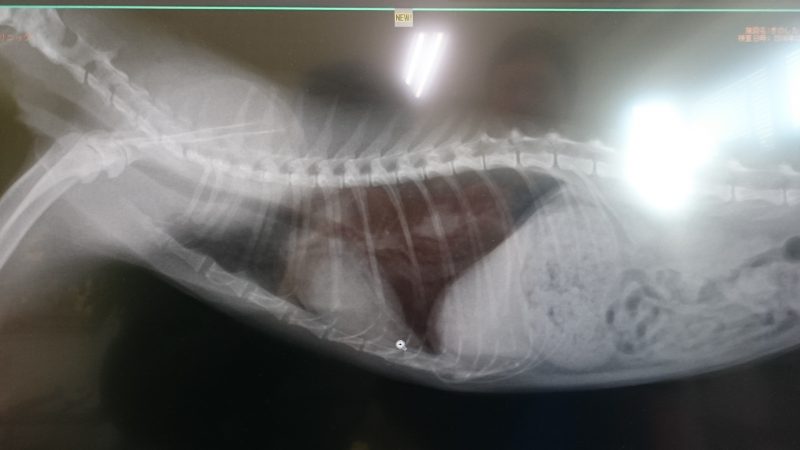

左肺に転移4ヵ所あって、抗がん剤が効いて、今のままを少しでも現状維持ができればの話で、2ヶ月~3ヶ月生きることができだろう。

おっぱいは4つあるけど、下から2番目の乳腺腫瘍にもかかわらず、もうすでにひだりの脇のリンパ節を通り、肺に4ヵ所の転移を起こしていました。

藤井先生も肺転移のレントゲンを見て、一番上までとってもおっちゃんには意味がないとの判断ということで、それは懸命な判断でしたねと、木下先生はおっしゃて、乳腺全摘出によるおとめちゃんへのメリットはもうありません。

進行の早さについては、藤井先生のオペの時のレントゲンと今日のレントゲンを比べたら、2週間でどれぐらい進行したかわかるから、見たいって言ってたけど、まだレントゲン画像が送られてないから分かりませんでした。